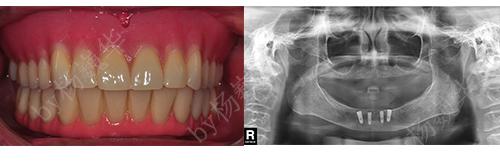

性别:女

年龄:68

主治医生:杨登

所在门诊:宁德中富口腔

主诉:下颌活动牙松动,咨询种植牙修复

治疗方案:下颌种植覆盖义齿修复(后来转为种植牙固定修复)

术后